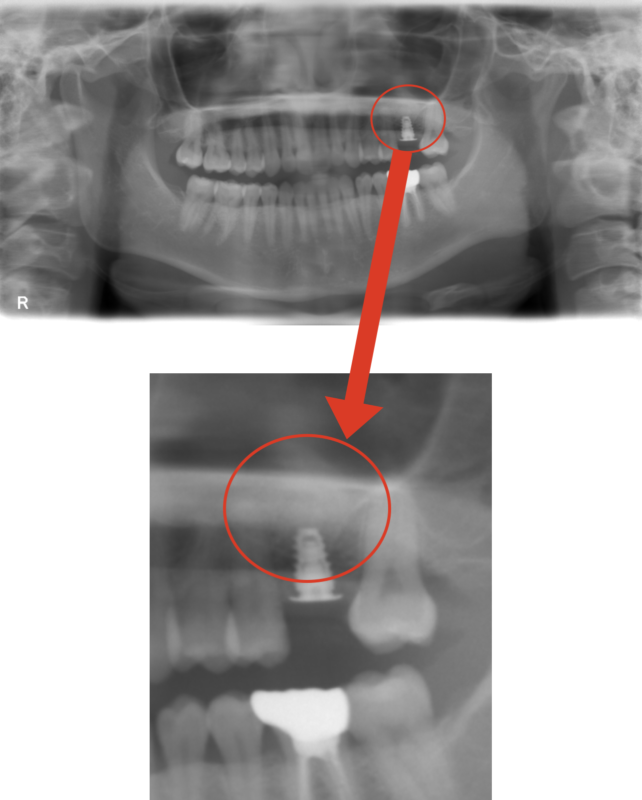

治療後写真

レントゲン上でも、骨がしっかりできていることがわかります。

予後も問題なく、しっかり噛めるようになりました。